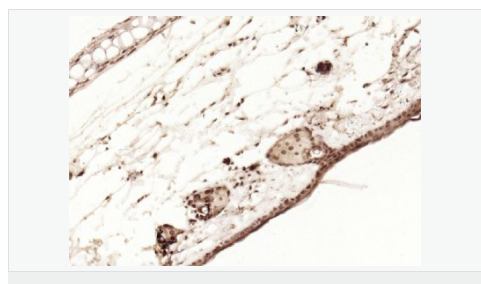

| 產(chǎn)品應(yīng)用 | WB=1:1000-2000 ELISA=1:1000-5000 IHC-P=1:100-500 IHC-F=1:100-500 Flow-Cyt=1ug/Test ICC=1:100-500 IF=1:100-500 (石蠟切片需做抗原修復(fù)) not yet tested in other applications. optimal dilutions/concentrations should be determined by the end user. |

| 細(xì)胞定位 | 細(xì)胞核 細(xì)胞漿 |

| 產(chǎn)品介紹 | p53, a DNA-binding, oligomerization domain- and transcription activation domain-containing tumor suppressor, upregulates growth arrest and apoptosis-related genes in response to stress signals, thereby influencing programmed cell death, cell differentiation, and cell cycle control mechanisms. p53 localizes to the nucleus, yet can be chaperoned to the cytoplasm by the negative regulator, MDM2. MDM2 is an E3 ubiquitin ligase that is upregulated in the presence of active p53, where it poly-ubiquitinates p53 for proteasome targeting. p53 fluctuates between latent and active DNA-binding conformations and is differentially activated through posttranslational modifications, including phosphorylation and acetylation. Mutations in the DNA-binding domain (DBD) of p53, amino acids 110-286, can compromise energetically-favorable association with cis elements and are implicated in several human cancers. Function: [FUNCTION] Acts as a tumor suppressor in many tumor types; induces growth arrest or apoptosis depending on the physiological circumstances and cell type. Involved in cell cycle regulation as a trans-activator that acts to negatively regulate cell division by controlling a set of genes required for this process. One of the activated genes is an inhibitor of cyclin-dependent kinases. Apoptosis induction seems to be mediated either by stimulation of BAX and FAS antigen expression, or by repression of Bcl-2 expression. Implicated in Notch signaling cross-over. Prevents CDK7 kinase activity when associated to CAK complex in response to DNA damage, thus stopping cell cycle progression. Isoform 2 enhances the transactivation activity of isoform 1 from some but not all TP53-inducible promoters. Isoform 4 suppresses transactivation activity and impairs growth suppression mediated by isoform 1. Isoform 7 inhibits isoform 1-mediated apoptosis. Subunit: Interacts with AXIN1. Probably part of a complex consisting of TP53, HIPK2 and AXIN1 (By similarity). Binds DNA as a homotetramer. Interacts with histone acetyltransferases EP300 and methyltransferases HRMT1L2 and CARM1, and recruits them to promoters Subcellular Location: Cytoplasm. Nucleus. Nucleus, PML body. Endoplasmic reticulum. Note=Interaction with BANP promotes nuclear localization. Recruited into PML bodies together with CHEK2. Tissue Specificity: Ubiquitous. Isoforms are expressed in a wide range of normal tissues but in a tissue-dependent manner. Isoform 2 is expressed in most normal tissues but is not detected in brain, lung, prostate, muscle, fetal brain, spinal cord and fetal liver. Isoform 3 is expressed in most normal tissues but is not detected in lung, spleen, testis, fetal brain, spinal cord and fetal liver. Isoform 7 is expressed in most normal tissues but is not detected in prostate, uterus, skeletal muscle and breast. Isoform 8 is detected only in colon, bone marrow, testis, fetal brain and intestine. Isoform 9 is expressed in most normal tissues but is not detected in brain, heart, lung, fetal liver, salivary gland, breast or intestine. Post-translational modifications: Acetylated. Acetylation of Lys-382 by CREBBP enhances transcriptional activity. Deacetylation of Lys-382 by SIRT1 impairs its ability to induce proapoptotic program and modulate cell senescence. Phosphorylation on Ser residues mediates transcriptional activation. Phosphorylated by HIPK1. Phosphorylation at Ser-9 by HIPK4 increases repression activity on BIRC5 promoter. Phosphorylated on Thr-18 by VRK1. Phosphorylated on Ser-20 by CHEK2 in response to DNA damage, which prevents ubiquitination by MDM2. Phosphorylated on Ser-20 by PLK3 in response to reactive oxygen species (ROS), promoting p53/TP53-mediated apoptosis. Phosphorylated on Thr-55 by TAF1, which promotes MDM2-mediated degradation. Phosphorylated on Ser-33 by CDK7 in a CAK complex in response to DNA damage. Phosphorylated on Ser-46 by HIPK2 upon UV irradiation. Phosphorylation on Ser-46 is required for acetylation by CREBBP. Phosphorylated on Ser-392 following UV but not gamma irradiation. Phosphorylated upon DNA damage, probably by ATM or ATR. Phosphorylated on Ser-15 upon ultraviolet irradiation; which is enhanced by interaction with BANP. Phosphorylated by NUAK1 at Ser-15 and Ser-392; was initially thought to be mediated by STK11/LKB1 but it was later shown that it is indirect and that STK11/LKB1-dependent phosphorylation is probably mediated by downstream NUAK1 (PubMed:21317932). It is unclear whether AMP directly mediates phosphorylation at Ser-15. Phosphorylated on Thr-18 by isoform 1 and isoform 2 of VRK2. Phosphorylation on Thr-18 by isoform 2 of VRK2 results in a reduction in ubiquitination by MDM2 and an increase in acetylation by EP300. Stabilized by CDK5-mediated phosphorylation in response to genotoxic and oxidative stresses at Ser-15, Ser-33 and Ser-46, leading to accumulation of p53/TP53, particularly in the nucleus, thus inducing the transactivation of p53/TP53 target genes. Phosphorylated at Ser-315 and Ser-392 by CDK2 in response to DNA-damage. Dephosphorylated by PP2A-PPP2R5C holoenzyme at Thr-55. SV40 small T antigen inhibits the dephosphorylation by the AC form of PP2A. May be O-glycosylated in the C-terminal basic region. Studied in EB-1 cell line. Ubiquitinated by MDM2 and SYVN1, which leads to proteasomal degradation. Ubiquitinated by RFWD3, which works in cooperation with MDM2 and may catalyze the formation of short polyubiquitin chains on p53/TP53 that are not targeted to the proteasome. Ubiquitinated by MKRN1 at Lys-291 and Lys-292, which leads to proteasomal degradation. Deubiquitinated by USP10, leading to its stabilization. Ubiquitinated by TRIM24, which leads to proteasomal degradation. Ubiquitination by TOPORS induces degradation. Deubiquitination by USP7, leading to stabilization. Isoform 4 is monoubiquitinated in an MDM2-independent manner. Monomethylated at Lys-372 by SETD7, leading to stabilization and increased transcriptional activation. Monomethylated at Lys-370 by SMYD2, leading to decreased DNA-binding activity and subsequent transcriptional regulation activity. Lys-372 monomethylation prevents interaction with SMYD2 and subsequent monomethylation at Lys-370. Dimethylated at Lys-373 by EHMT1 and EHMT2. Monomethylated at Lys-382 by SETD8, promoting interaction with L3MBTL1 and leading to repress transcriptional activity. Demethylation of dimethylated Lys-370 by KDM1A prevents interaction with TP53BP1 and represses TP53-mediated transcriptional activation. Sumoylated by SUMO1. DISEASE: Note=TP53 is found in increased amounts in a wide variety of transformed cells. TP53 is frequently mutated or inactivated in about 60% of cancers. TP53 defects are found in Barrett metaplasia a condition in which the normally stratified squamous epithelium of the lower esophagus is replaced by a metaplastic columnar epithelium. The condition develops as a complication in approximately 10% of patients with chronic gastroesophageal reflux disease and predisposes to the development of esophageal adenocarcinoma. Similarity: Belongs to the p53 family. SWISS: P04637 Gene ID: 7157 Database links: Entrez Gene: 7157 Human Entrez Gene: 22059 Mouse Omim: 191170 Human SwissProt: P04637 Human SwissProt: P02340 Mouse Unigene: 654481 Human Unigene: 222 Mouse Unigene: 54443 Rat Important Note: This product as supplied is intended for research use only, not for use in human, therapeutic or diagnostic applications. |